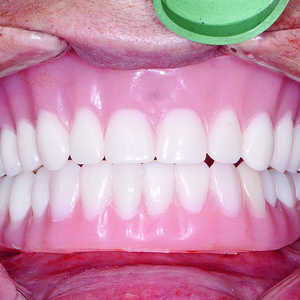

Les restaurations définitives ont été mises en place au cours de la visite suivante et montraient une adaptation, une fonction et une relation inter-occlusale précises (Figs. 21 et 22). Grâce à la phase d’essayage, aucun ajustement des prothèses en zircone monolithique n’a été nécessaire, car les bridges en PMMA avaient permis de définir précisément les modifications nécessaires à l’obtention de la forme et de l’esthétique parfaites. Une dernière radiographie a confirmé l’adaptation totale des restaurations en zircone BruxZir sur les piliers implantaires personnalisés Inclusive. La patiente s’est montrée extrêmement satisfaite de la reconstruction de ses arcades maxillaire et mandibulaire dont le rétablissement de l’esthétique et de la fonction dentaire lui avait rendu confort et confiance.

Fig-11-Insertion-d’un-implant-dentaire-Hahn-300x300-

Fig-21-Vue-des-dents-non-engrenées-300x300-